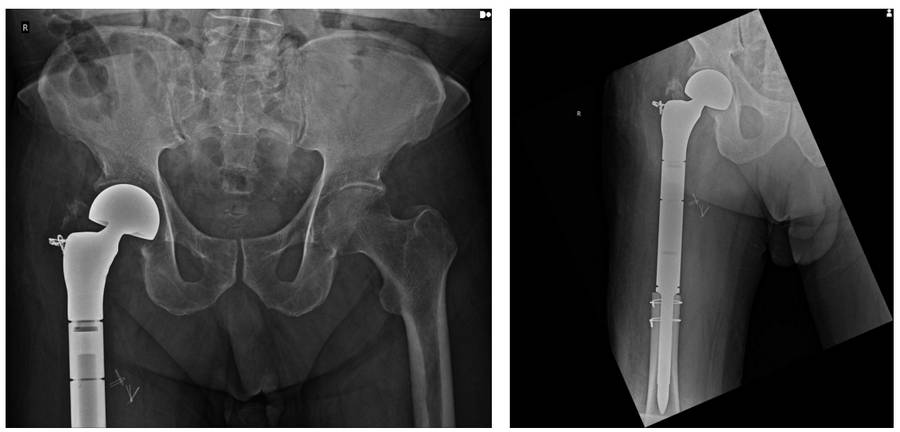

Post-Surgery: The X-ray shows reconstruction with a tumor prosthesis after proximal femur resection.